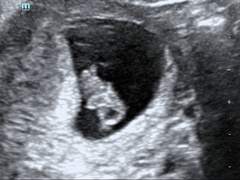

Had my private scan last night and baby is well, doing a headstand and measuring 8w5d today. So hard to get head around fact that's happening inside. Could see clear heart flicker, round head, arm and leg buds, and spine. Got some nice wee video clips too. Grin Time to try to chill out now!!